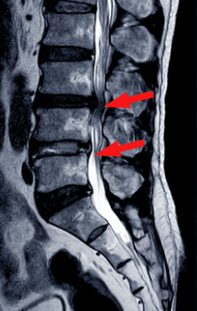

変形性腰椎症をベースに起こることが多く、高齢の方によく生じる病気です。変形性腰椎症と大きく違う点は、腰骨のズレや神経の周りの靭帯が分厚くなることで、神経の通り道が狭くなり、神経が圧迫されることです。脊柱管という腰骨の中の神経の通り道が狭くなるため、腰部脊柱管狭窄症と呼ばれます。症状としては、腰痛よりも足のしびれや痛みが出やすいです。特にお尻や太ももの外側・後ろ、ふくらはぎのしびれ痛みを生じ、歩くとどんどん痛みが強くなり、数十メートルも歩けなくなってしまう方もいます。前かがみの姿勢で足の痛みが楽になることが多いため、自転車を乗るときは痛みを感じない方がいらっしゃいます。

足のしびれ痛みの範囲、跛行(歩いてどんどん痛くなること)の有無、足に力が入るかをチェックします。足の血管が詰まっても同じような症状となるので、足の甲の動脈が触れるかを確認することもあります。レントゲンで腰骨の並びもチェックしますが、神経の通り道が本当に細くなっているかはMRIを撮像しないとわからないため、症状が酷い方にはMRIを撮ることを推奨してます。